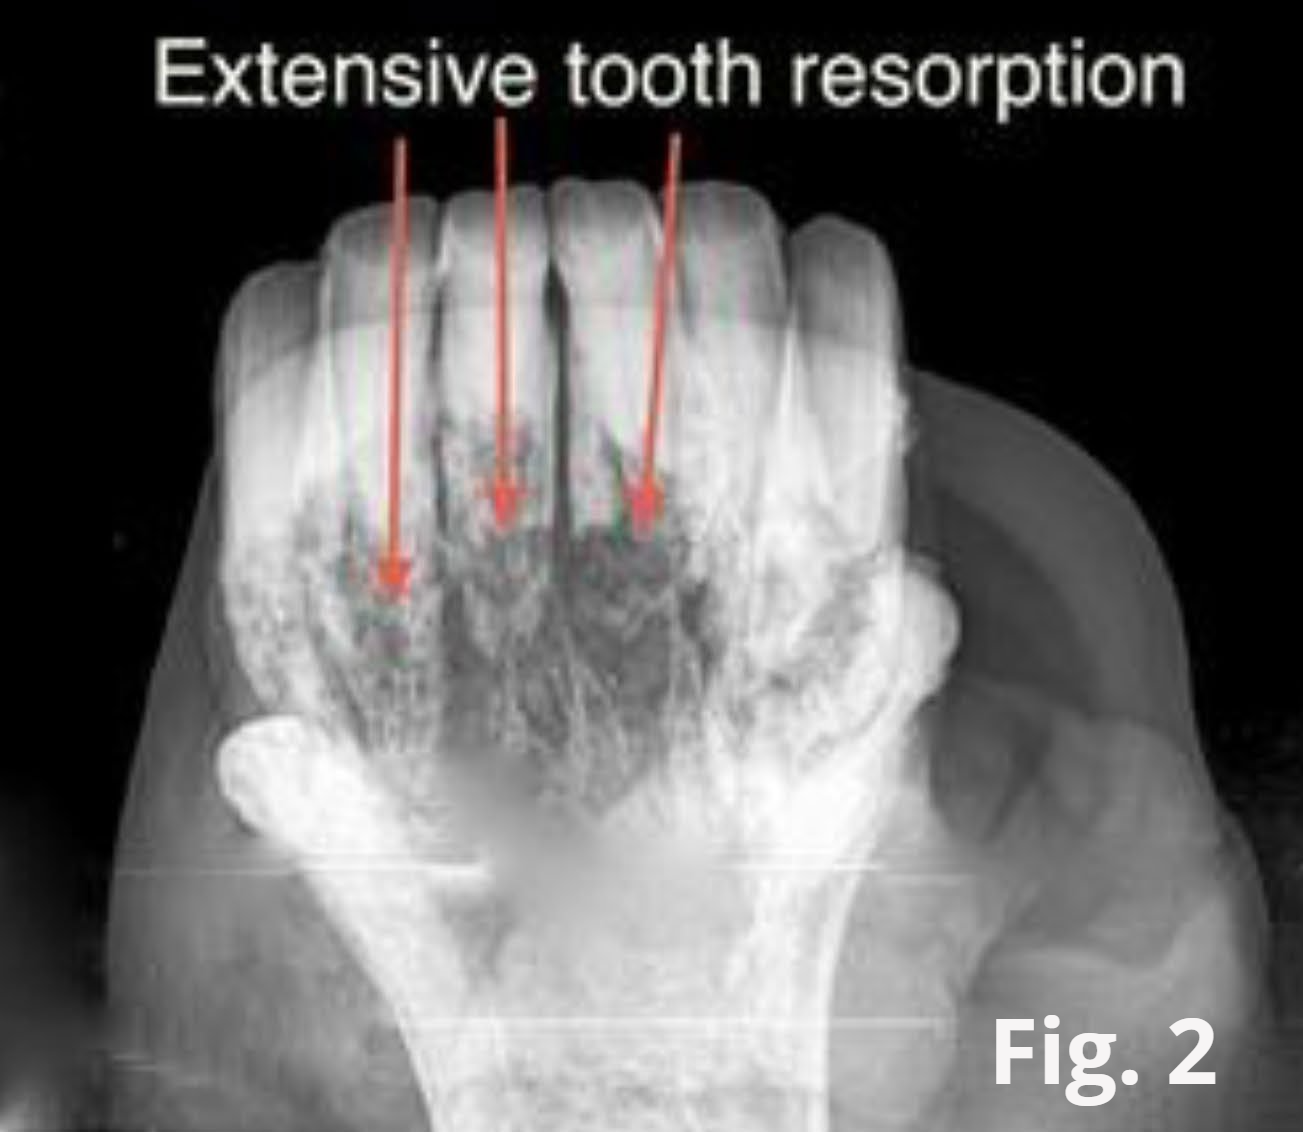

The progression of EORTH is marked by severe tooth root resorption. The body basically degrades the tooth root and supporting structures of the tooth. This results in the affected teeth becoming loose. In an attempt to stabilize itself, the tooth responds by producing large amounts of cementum. This overproduction of cementum can give the gum tissue a bulbous appearance (see fig. 1). The instability of the teeth will result in a severe inflammatory response and underlying infection. When the disease has progressed to this point, your horse will be experiencing severe pain.